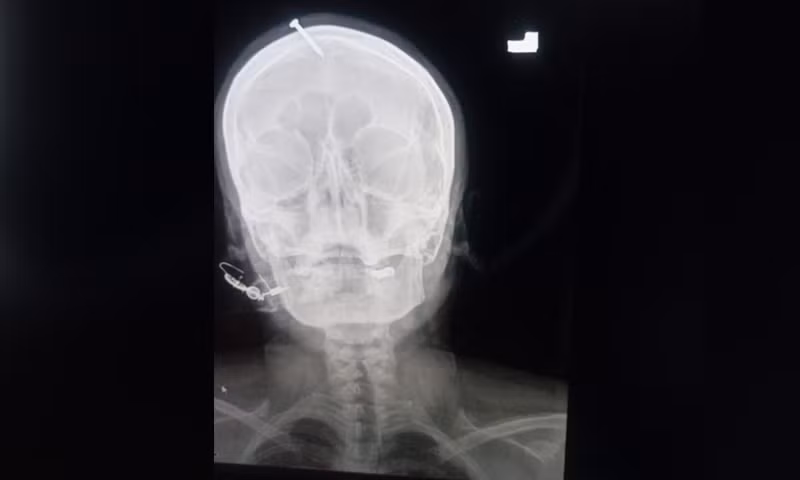

| Ảnh chụp X-quang cho thấy chiếc đinh đóng vào đầu thai phụ. |